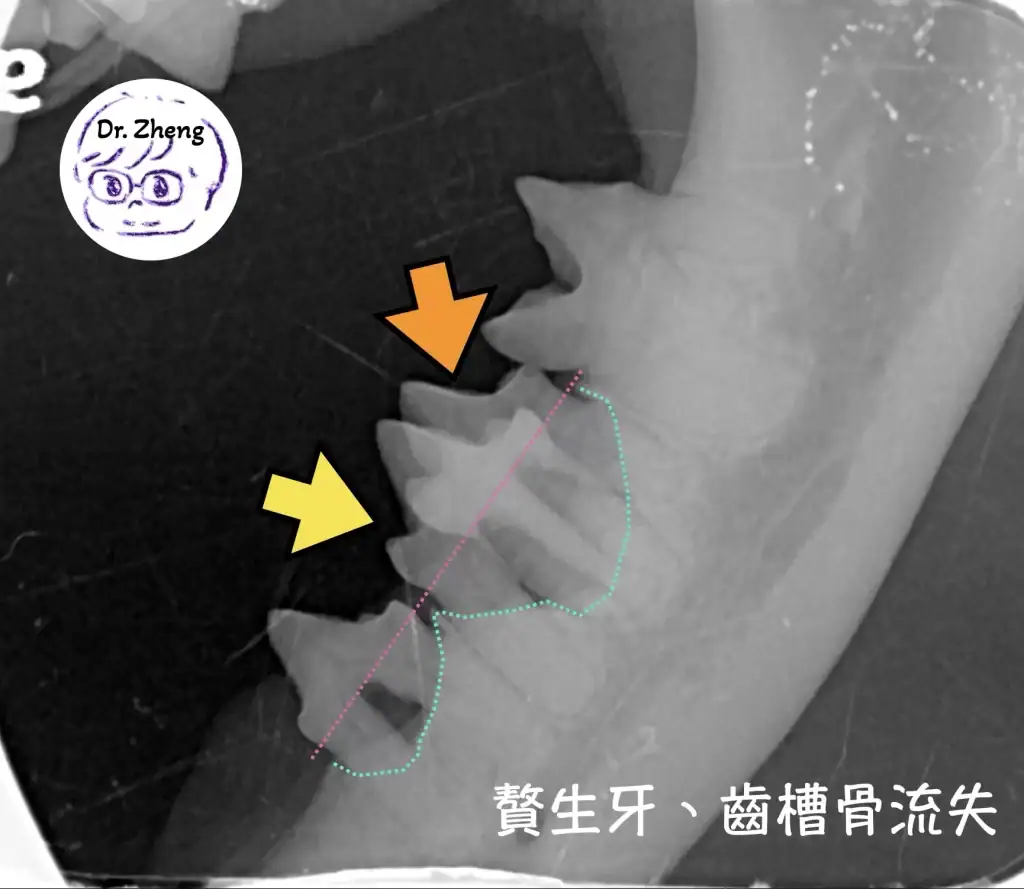

牙科X光檢查

口腔內出現多餘的牙齒,會使得有更多死角讓細菌得以藏匿,最終引發牙周病!

透過牙科X光我們得以評估牙根與鄰近結構的關係!